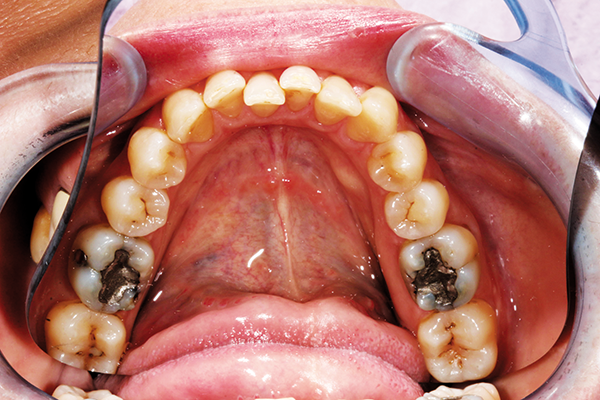

A fearful patient seeking multidisciplinary changes needed treatment of decayed bilateral lower molars. The goal was to preserve tooth structure and restore directly (Fig. 4).

Fig. 4 Fig. 5

Restoring the posterior molars was easily done with BRILLIANT EverGlow. It was easily condensed and sculpted to anatomical contours and polished to a lifelike shine (Fig. 5).